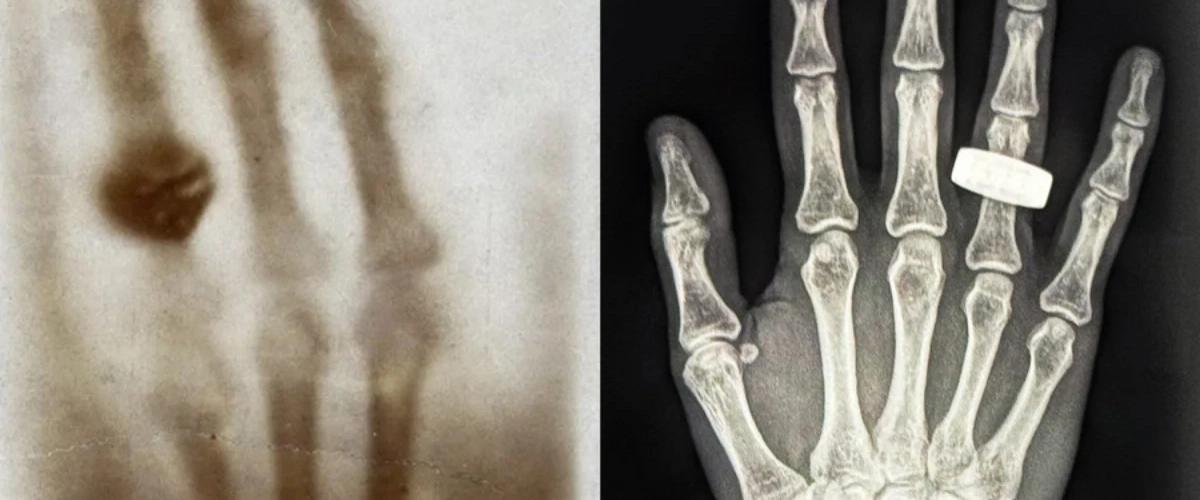

Главная цель эксперимента — проверить, можно ли делать рентгеновские снимки в космосе с достаточным качеством для диагностики. Это нужно знать для будущих дальних экспедиций, при которых на борту не будет врачей или оборудования, к которым привыкли на Земле. В проекте участвовали специалисты Массачусетского технологического института (MIT), Стэнфордского университета, клиники Мейо, а также компании KA Imaging и MinXray, которые адаптировали портативное рентгеновское оборудование, изначально разработанное для применения на поле боя.

Она отметила и другие сложности. Например, радиационный фон на орбите может мешать получению чётких изображений, а человек в условиях невесомости не фиксируется в нужном положении, как на Земле. Однако первый полученный снимок оказался отличного качества. Петерсен с нетерпением ждёт возможности проанализировать остальные кадры.

Команда Fram2 освоила процедуру всего за один день. По разработанному протоколу астронавты фотографировали друг друга, проверяли результат и сохраняли снимки. Пока что опубликовали только один, но даже он показывает, насколько хорошо участники полёта справились.

Теперь астронавты смогут проверять состояние костей, выявлять переломы, следить за признаками потери кальция в костной ткани и даже оценивать наличие жидкости в лёгких. До этого такие исследования в космосе не проводились.